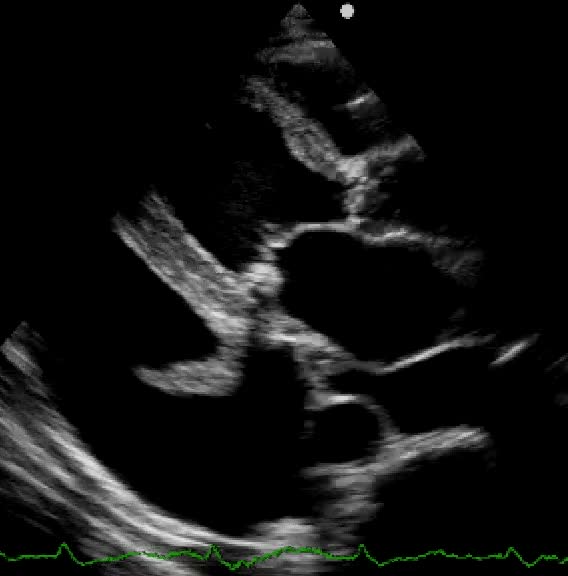

Miectomia settale estesa sec morrow

Paolo Ferrazzi